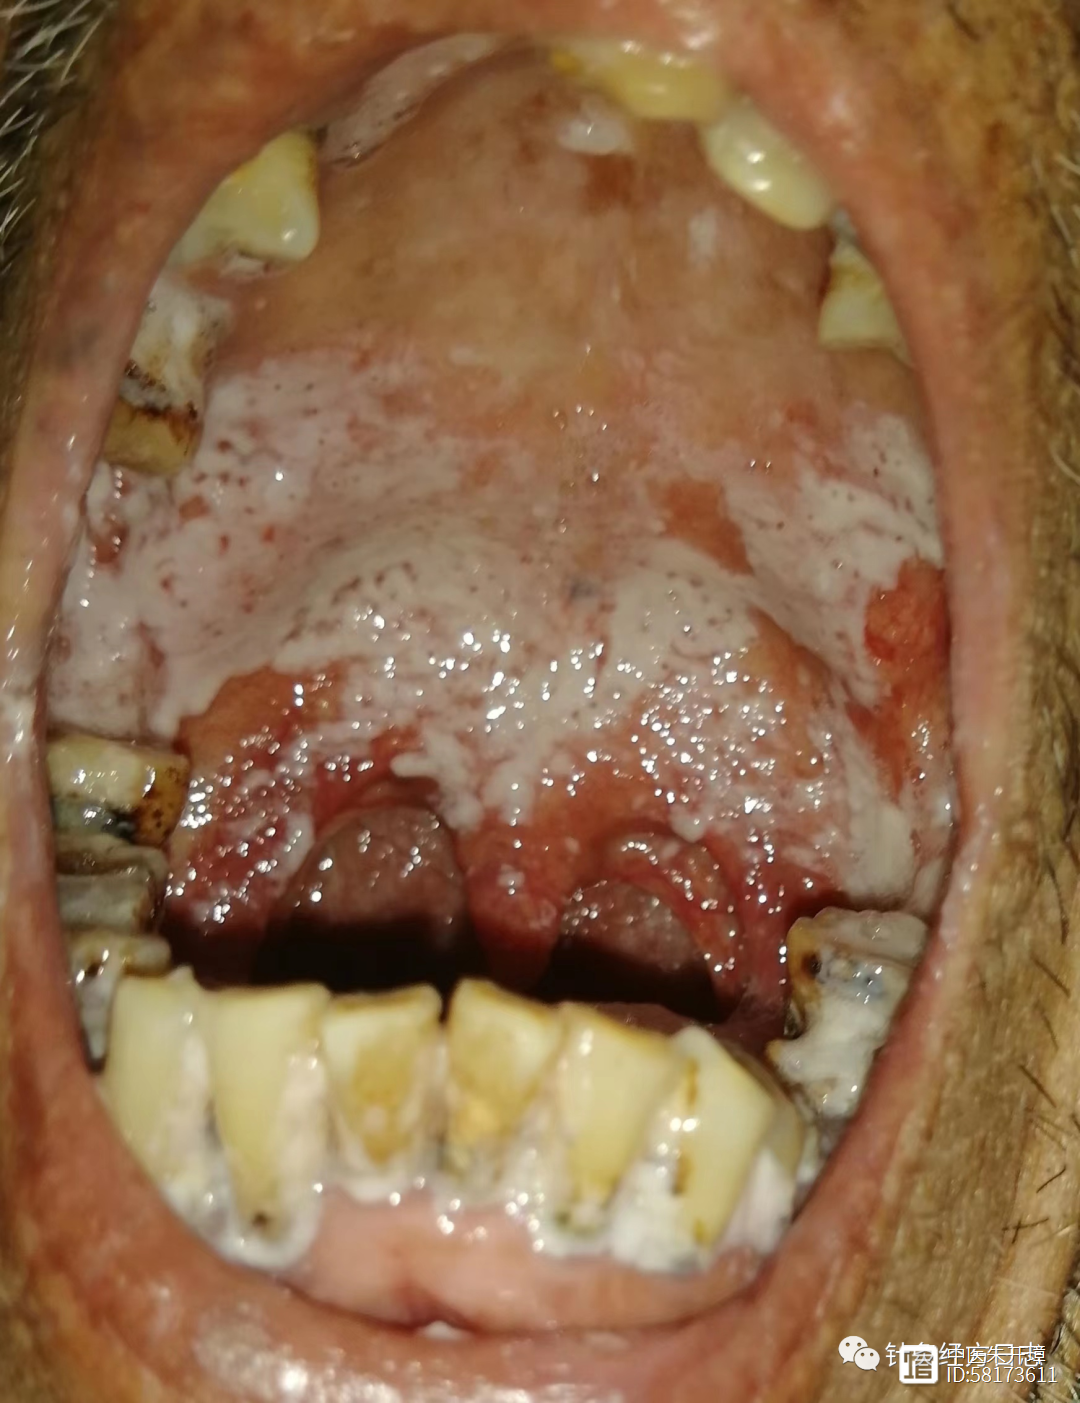

今天查房时,一位患者轻声问我:“李主任,我已经是晚期了,癌细胞也扩散了,还能活多久?还有必要化疗吗?” 这个问题背后,是许多晚期癌症患者共同的迷茫与焦虑。作为医生,我想和您聊聊这个话题。01“癌细胞扩散还能活多久?”...